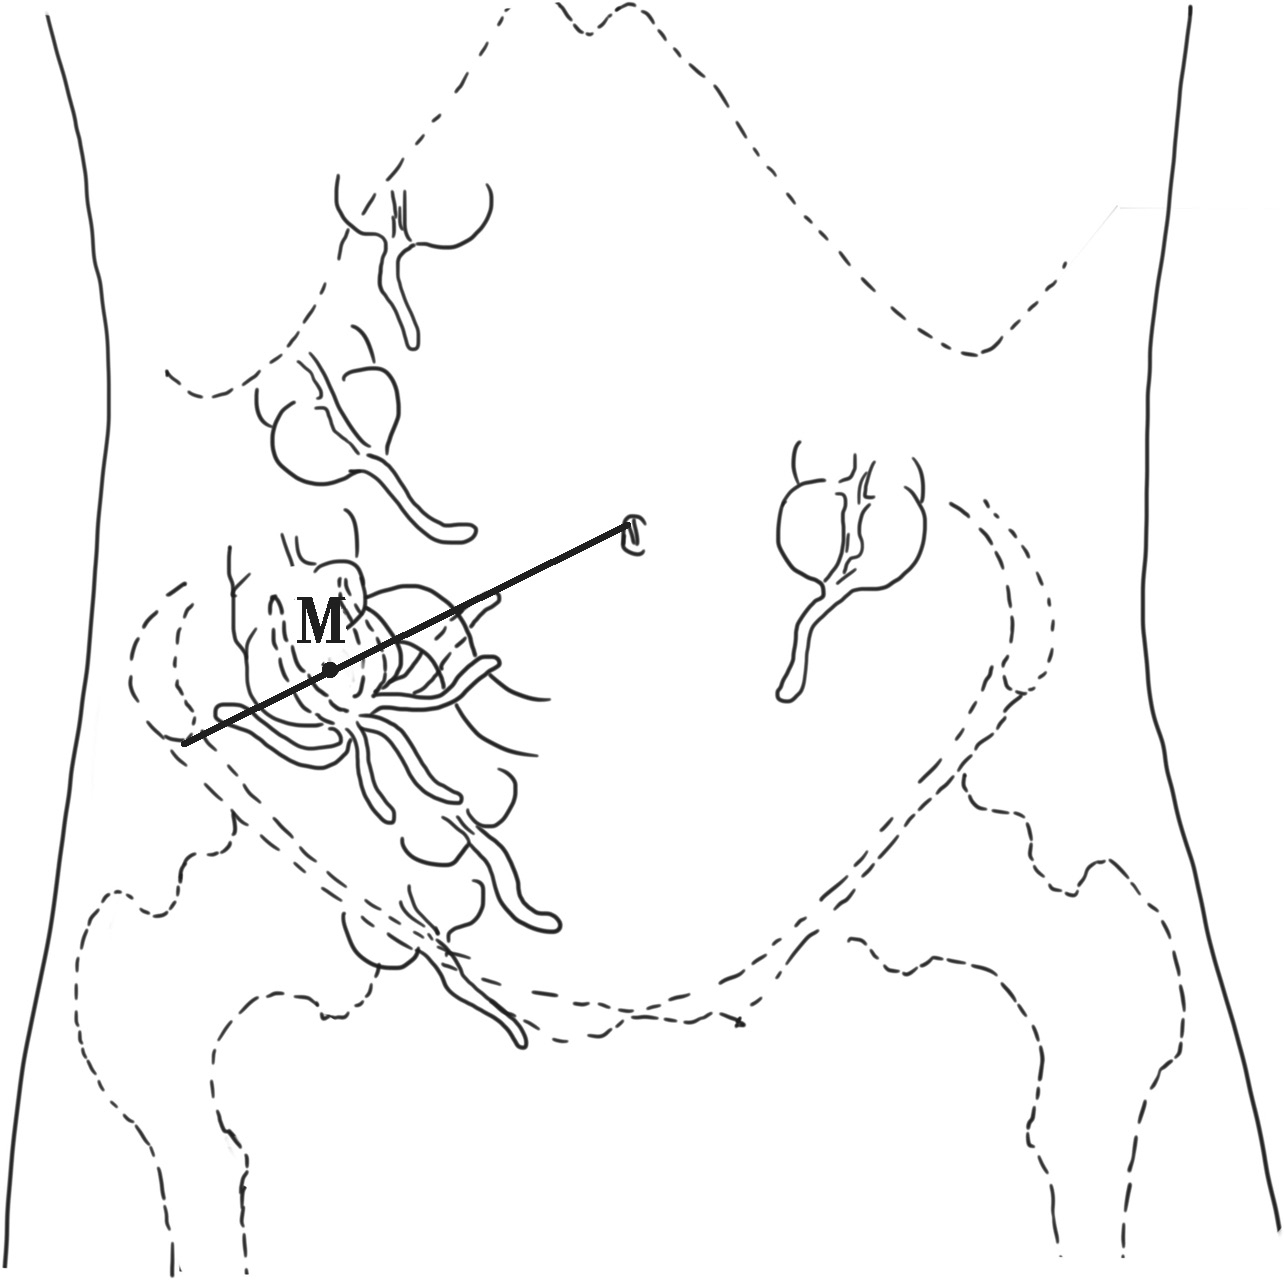

阑尾是附属于盲肠的一段肠管,多位于右髂窝内,长度一般为2~10cm,直径0.2~0.6cm,形态变异大。阑尾是腹膜内位器官,有三角形的系膜悬于肠系膜下端,阑尾根部连于盲肠后内侧壁,较固定,是3条结肠带汇聚的位置。因其尖端位置可变,炎症时产生的症状、体征也不同。据统计,国人阑尾常见位置有(图2-3):①回肠前位,约占28%;②盆位,约占26%;③盲肠后位,约占24%;④回肠后位,约占8%;⑤盲肠下位,约占6%;⑥高位阑尾(肝右叶下方)、盲肠壁浆膜下阑尾及左下腹阑尾,极少见。

图2-3 阑尾位置的变异(M为麦氏点)